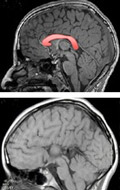

Des équipes de l'Institut de génétique et de biologie moléculaire et cellulaire (IGBMC, CNRS/Inserm/Unistra), entre autres, viennent d'identifier le premier gène à l'origine d'un défaut de développement du corps calleux : la principale structure cérébrale responsable de la communication entre les deux hémisphères du cerveau.

© Ch.Depienne